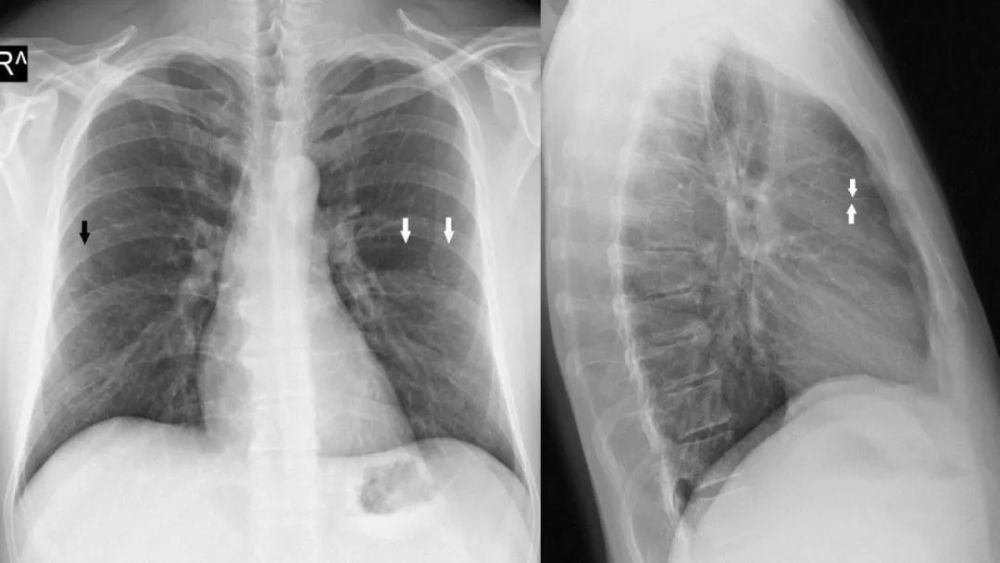

上副裂/叶

Superior accessory fissure

右肺下叶的上副叶 , 位于水平裂后方 , 将右肺下叶分为 上和基底段 , 称为后叶或背叶( posterior or dorsallobe)

可以完整或不完整 右肺多

>下附裂

左侧水平裂

Left minor fissure

CT上的检出率为:8% , AP胸片为1.6%

左侧水平裂将舌叶从下叶其它部分分隔出来 舌叶仍然保留其上段和下段 , 不同于右肺中叶 内侧段和外侧段 , 因此左肺的段解剖保持完整